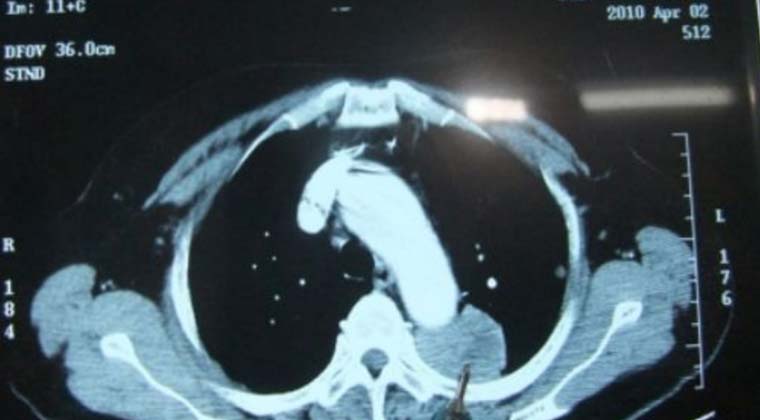

② Случай 2:

Очаговое образование в верхней доле левого легкого, прилежащее к аорте, вероятно является метастатической опухолью.

(Опухоль, на которую указывает кончик зонда)

(Область некроза опухолевой ткани, на которую указывает кончик зонда)